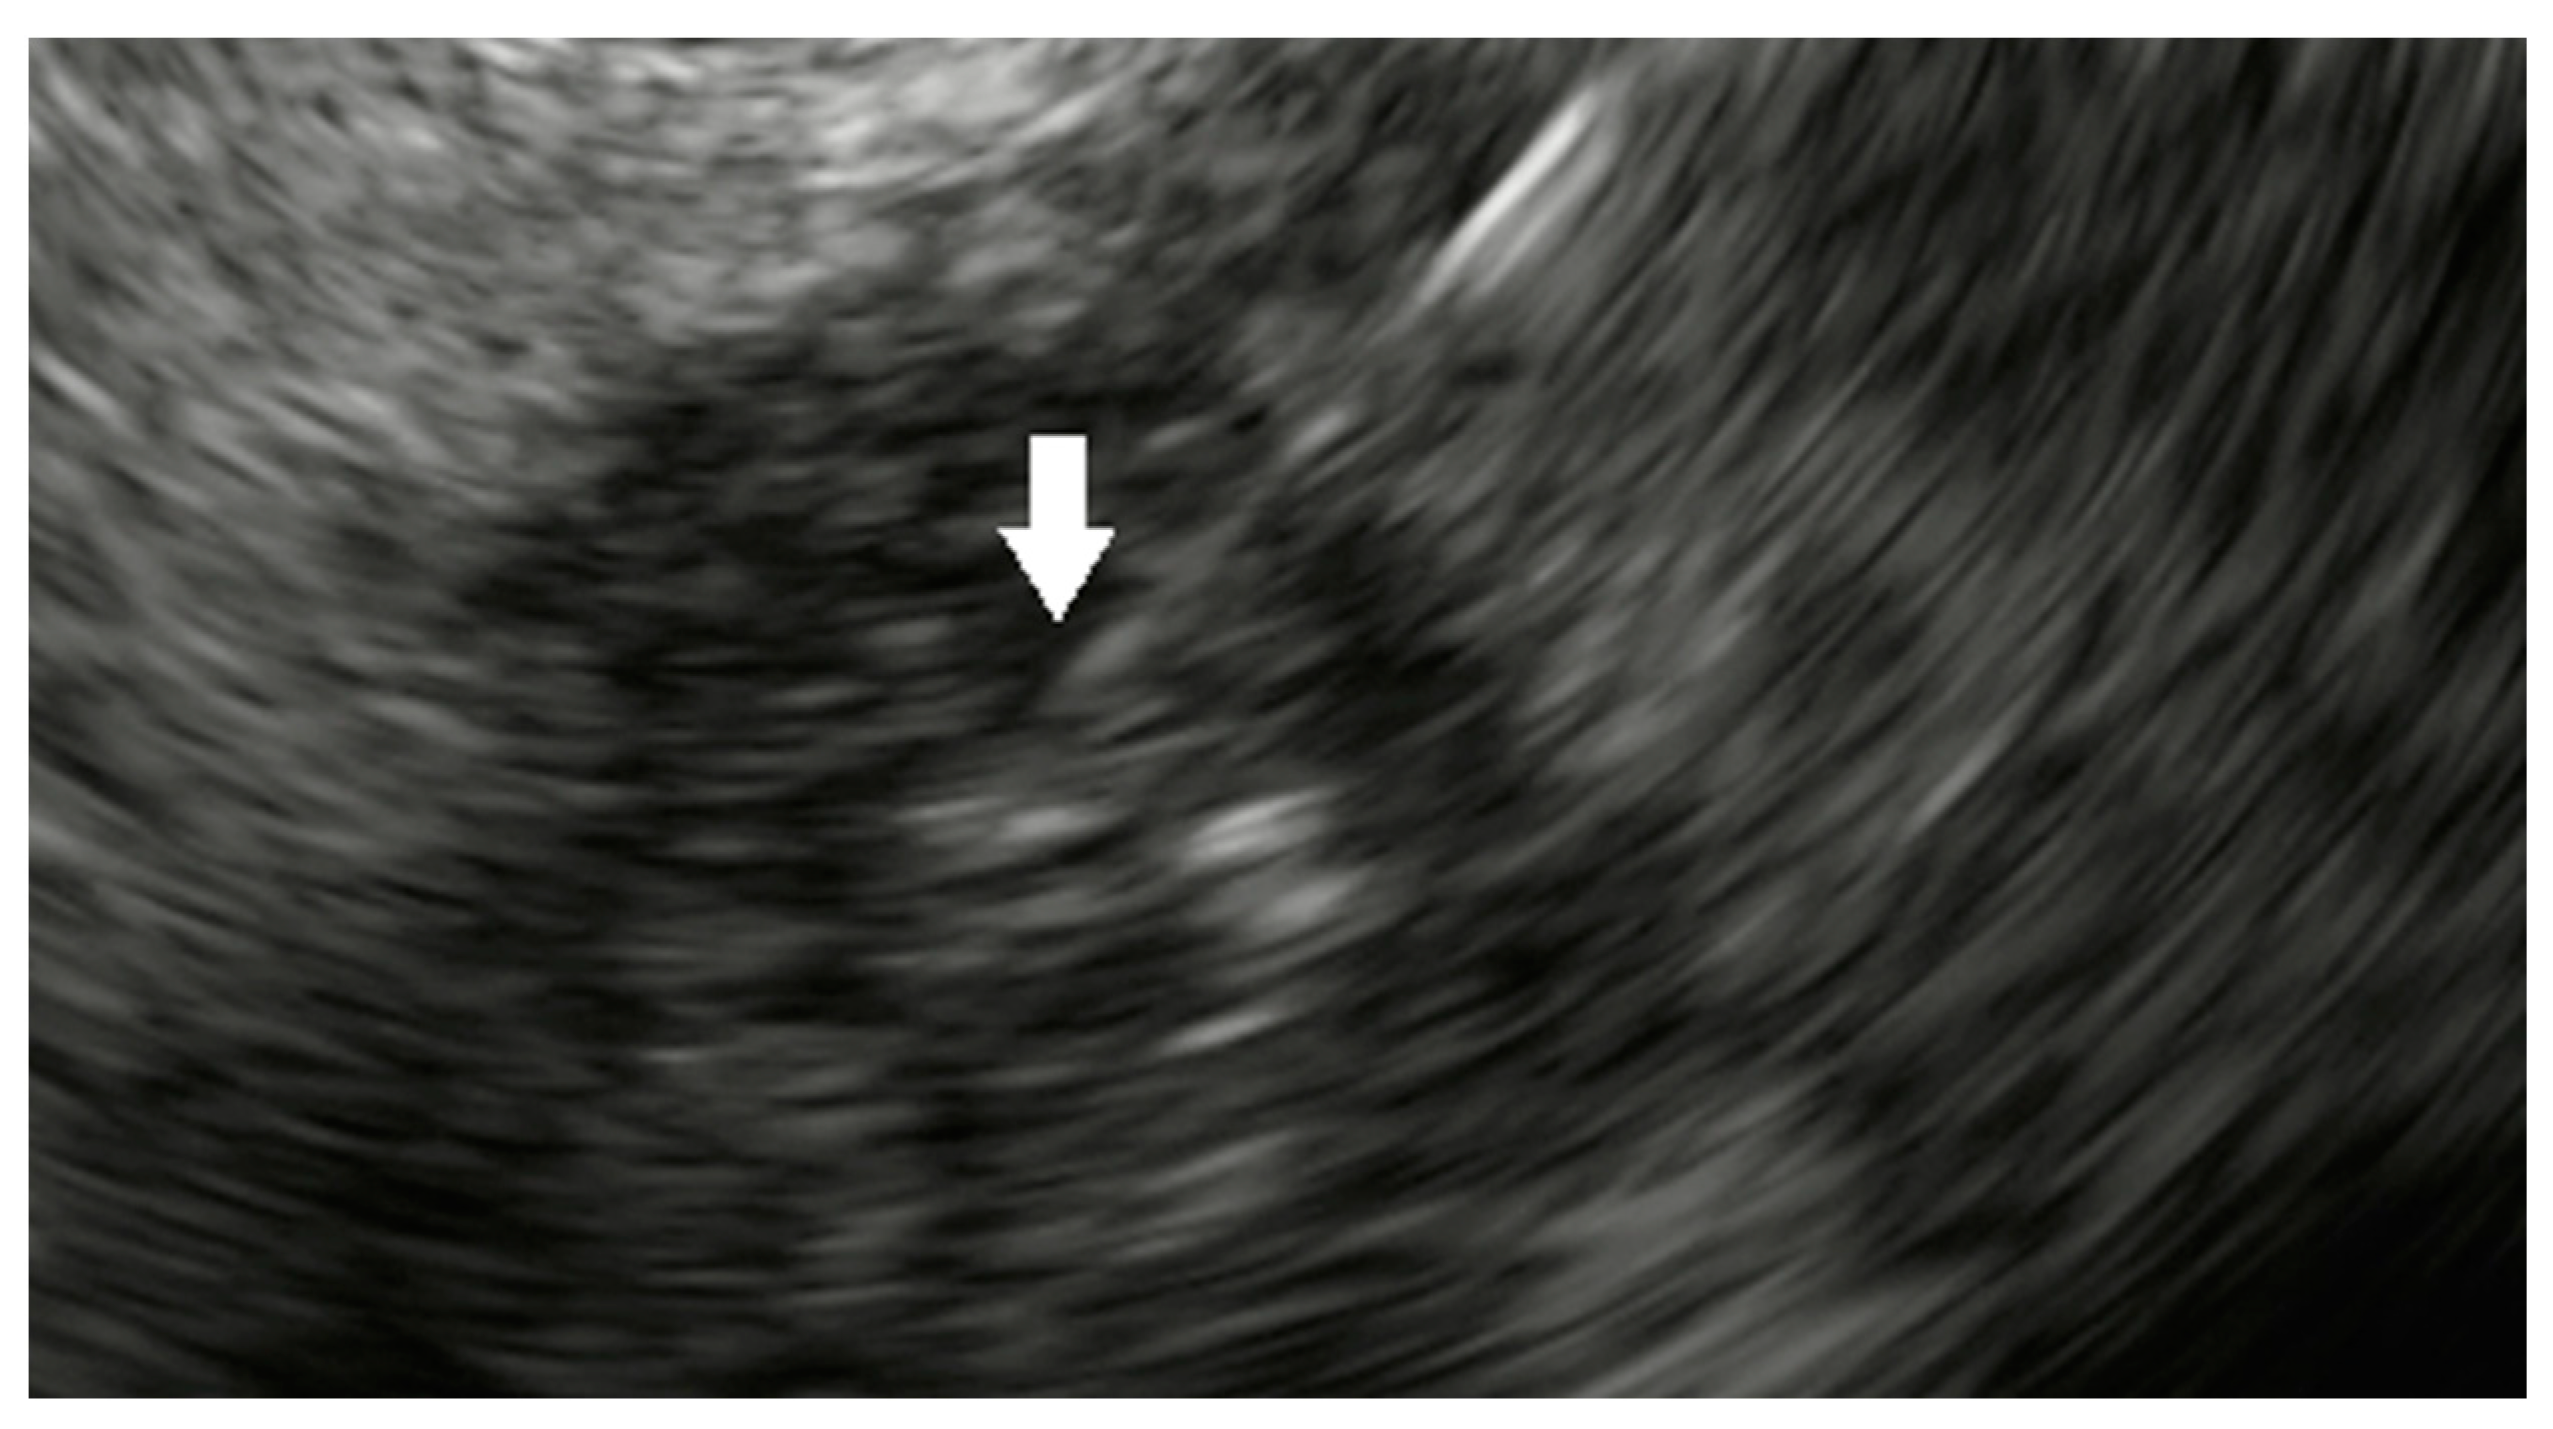

2.3.1. Radiofrequency Ablation

2.3.2. Hybrid Cryothermal Ablation